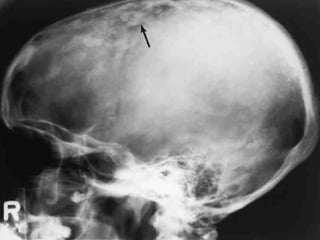

 This 18-year-old shows some of the clinical features of the nevoid

basal cell carcinoma syndrome including frontal bossing and

mandibular prognathism. B, The radiograph from another patient

shows a calcified falx cerebri.